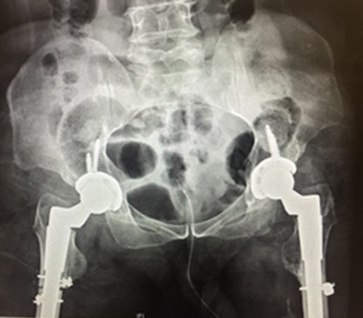

Some hips present with complex deformities. Examples are shown below. These hips often have had previous surgery resulting in severe stiffness or anatomical deformities. Others have significant congenital abnormalities like hip dislocation.

Careful pre-operative planning is done often using the OPS software analysis and an operative plan developed with attention to implant positioning and implant types. Surgery is performed via the posterior approach. Occasionally extra bone graft is required to the pelvis/acetabulum or even femoral bone shortening (in high congenital hip dislocation).

Recovery may include protected weight bearing on crutches for 6 weeks. These hips will usually take longer to recover but the end result is what counts.

These are examples of complex hip replacements: